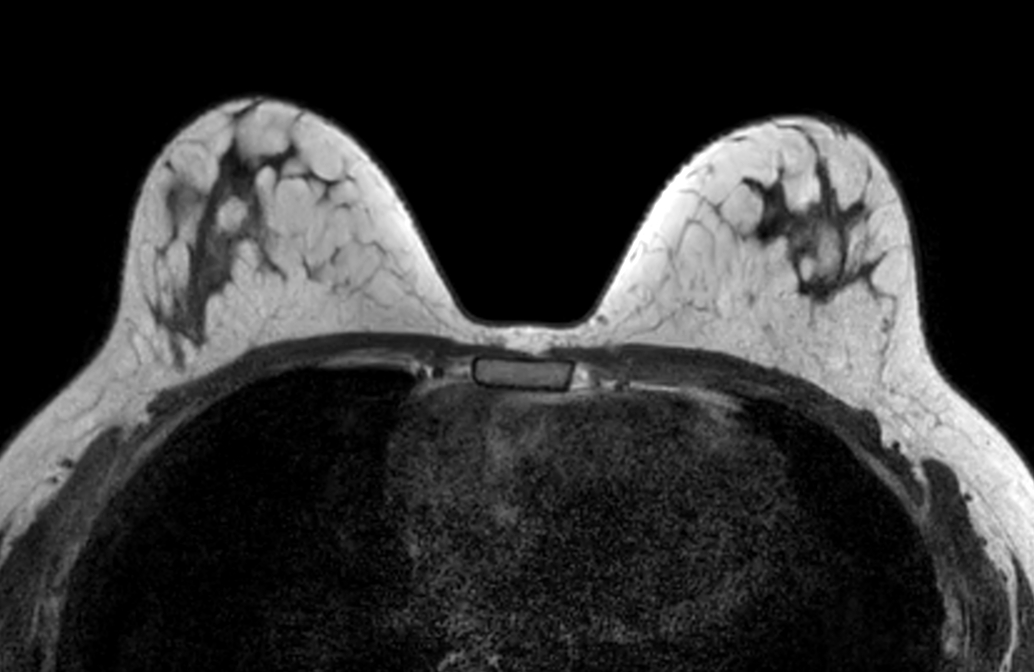

Axial T2w TSE